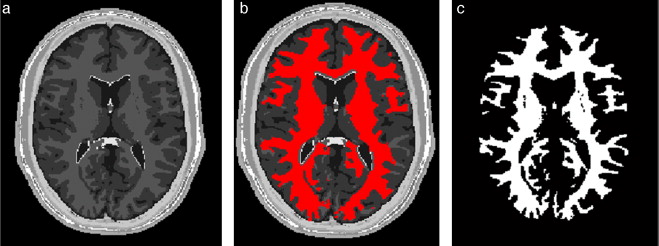

En la figura 10 se presenta el resultado de segmentar la materia blanca del cerebro en IRM empleando la rutina de Region Growing mencionada. En la figura 10 .a se observa la vista 3D del volumen inicial. En la figura 10 .b se observa uno de los cortes de la figura 10 .a con la selección de cuatro semillas iniciales de forma esférica dentro de la zona de la materia blanca. En la figura 10 .c se observa en color rojo la zona región de la materia blanca obtenida al finalizar la rutina de segmentación. En la figura 10 .d se presenta una vista 3D de la zona de la materia blanca segmentada.

|

|

|

Figura 10. Segmentación de materia blanca empleando Region Growing en IRM del cerebro. (a) Volumen formado por varios cortes de IRM cerebral original. (b) Vista de un corte coronal con la lección de cuatro semillas iniciales. (c) Vista del corte coronal (b) con la materia blanca segmentada con Region Growing . (d). Vista volumétrica de la materia blanca segmentada en (c). |

3.3.2. Segmentación

Se aplicó el algoritmo Region Growing sobre la imagen filtrada, colocando cuatro esferas (semillas) en la zona de interés, buscando ubicarlas en los extremos más arraigados de este tejido. La condición de inclusión utilizada para hacer crecer la región fue la descrita en la ecuación (10), en base a la media y la desviación estándar de los voxels vecinos. El volumen resultante fue una imagen binaria con la zona de la materia blanca coloreada en valores de 255 (blanco).

3.3.3. Remuestreo y exportación a CAD

Para mejorar el modelo geométrico inicial, se realizó el remuestreo del volumen a través de dilatación morfológica con un elemento estructural en forma de esfera de radio 3 × 3 × 3 a lo largo de todo el tejido segmentado. Este paso es necesario para suavizar superficies superpuestas y rellenar los agujeros generados durante la segmentación debido a la sensibilidad de la condición de segmentación. El modelo geométrico final fue guardado en formatos legibles por software de visualización y herramientas CAD como GiD, ParaView, Autodesk Inventor y Abaqus.

En la figura 20 se presentan los resultados obtenidos por cada etapa en imágenes médicas de IRM del cerebro en formato DICOM, 60 slices , tamaño de 256 × 256 pixels, voxel spacing: 0,86 × 0,86 mm × 3,0 mm . Por efectos de visualización, solamente se presenta uno de los cortes axiales utilizados. Obsérvese en la figura 20 .b la selección de cuatro semillas sobre la zona de interés, las cuales fueron asignadas de manera arbitraria. El éxito de la segmentación dependerá del lugar donde se coloquen estas semillas.

|

|

|

Figura 20. Segmentación de materia blanca empleando Region Growing en IRM del cerebro. (a) Volumen de IRM cerebral original. (b) Vista de un corte axial con la lección de cuatro semillas iniciales. (c) Imagen (b) filtrada con difusión anisotrópica. (d) Vista del corte axial (b) con la materia blanca segmentada a través de Region Growing . (e). Vista volumétrica de la materia blanca segmentada en (d). |